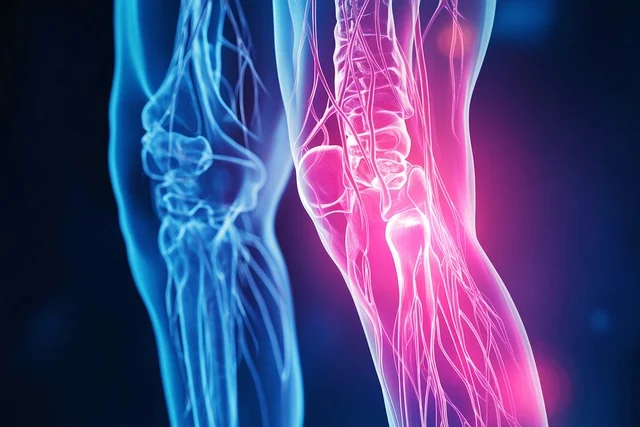

관절염은 관절 부위에 염증이 생기며 통증과 경직, 붓기 등을 유발하는 질환입니다. 관절염의 종류는 매우 다양하며, 퇴행성 관절염(골관절염)과 류마티스 관절염이 대표적입니다. 초기 단계에서 관절염의 증상을 알아차리고 관리하면 병의 진행을 늦추고 생활의 질을 유지하는 데 큰 도움이 됩니다. 이번 글에서는 관절염의 초기 증상, 종류별 차이, 예방법과 관리 방법에 대해 상세히 알려드리겠습니다.

퇴행성 관절염은 노화나 반복적인 관절 사용으로 인해 연골이 닳아 발생합니다. 주로 무릎, 엉덩이, 손가락 관절에서 자주 나타납니다.